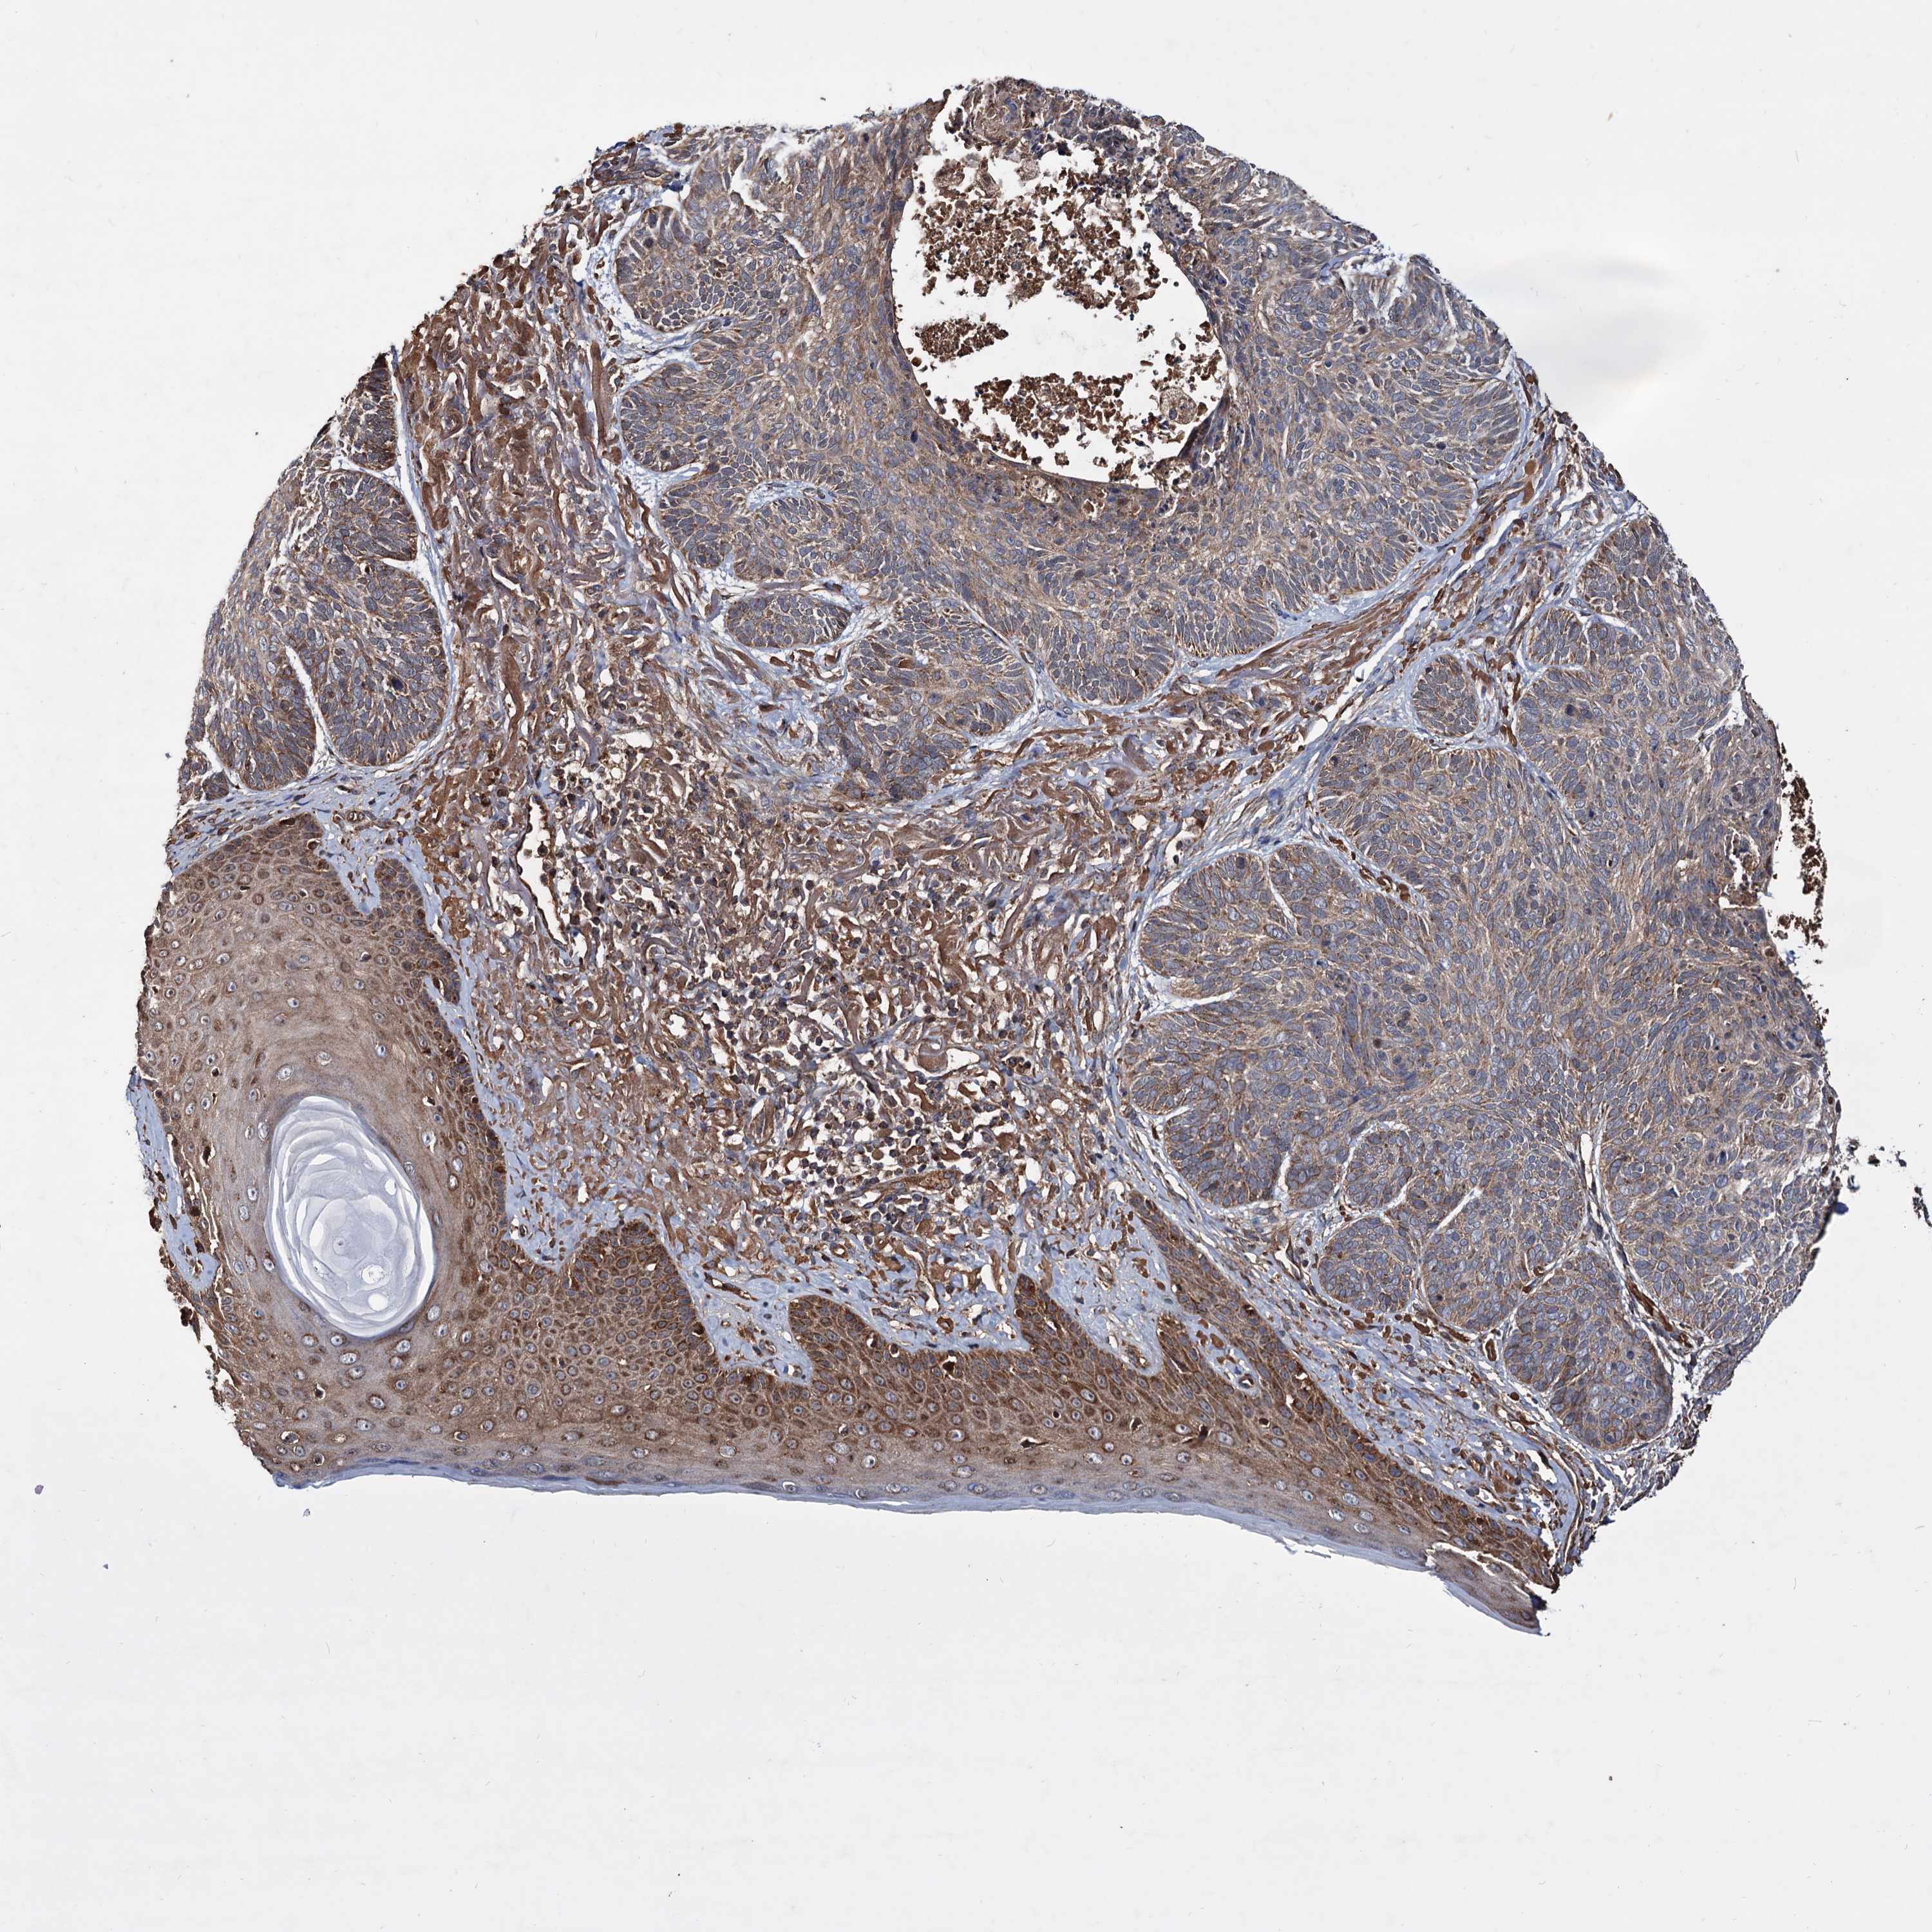

SKIN CANCER - Protein expressioni

A mouse-over function shows sample information and annotation data. Click on an image to view it in a full screen mode. Samples can be filtered based on level of antibody staining by selecting one or several of the following categories: high, medium, low and not detected. The assay and annotation is described here.

Antibody stainingi

Antibody staining in the annotated cell types in the current human tissue is reported as not detected, low, medium, or high, based on conventional immunohistochemistry profiling in selected tissues. This score is based on the combination of the staining intensity and fraction of stained cells.

Each image is clickable and will lead to virtual microscopy that enables deeper exploration of all samples and also displays staining intensity scores, fraction scores and subcellular localization as well as patient and tissue information for each sample.

Antibody HPA039398

Staining

High

Medium

Low

Not detected

Intensity

Strong

Moderate

Weak

Negative

Quantity

>75%

75%-25%

<25%

None

Location

Nuclear

Cytoplasmic/membranous

Cytoplasmic/membranous,nuclear

Squamous cell carcinoma, NOS